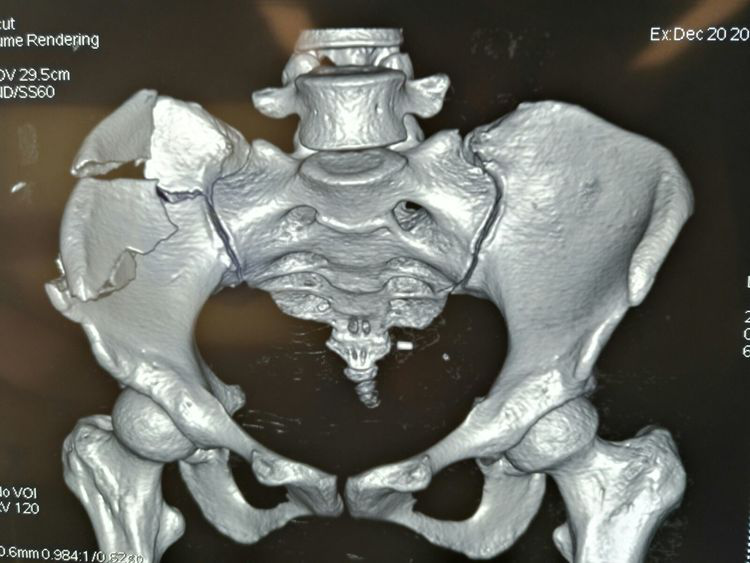

術(shù)前CT三維重建影像

術(shù)前CT三維重建